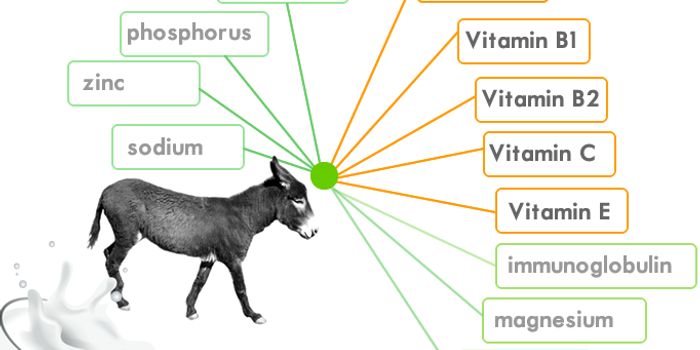

JUL 21, 2015Health & MedicineThe use of donkey milk dates back to 460-370 B.C. when Hippocrates, the father of medicine, reportedly would prescribe d ...